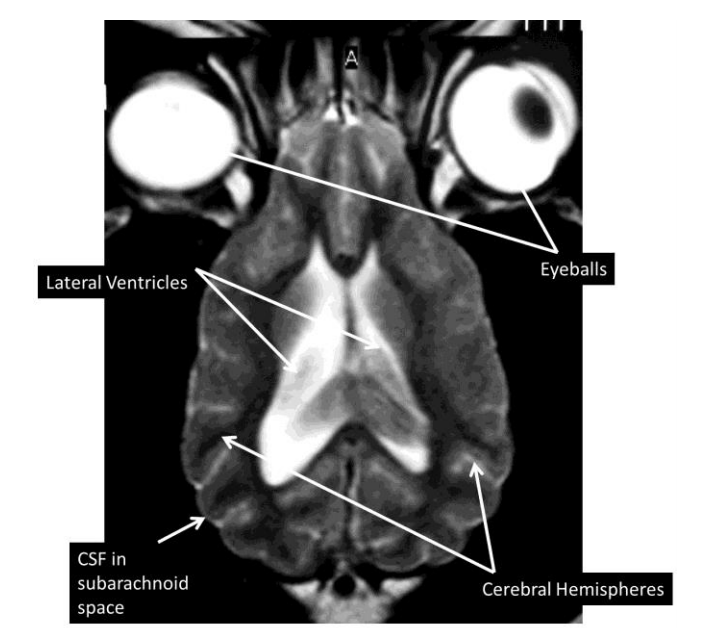

what are the structures shown

identify the structures

what are the species differences between cat and dog (shape, proportional sizes of the cerebral hemispheres and cerebellum)

the lateral ventricles are smaller in cats than in dogs